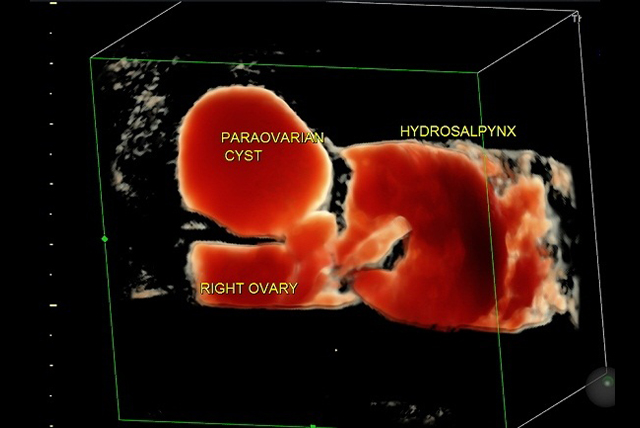

✔️ Ultrasound assessment for management of ovarian masses, pelvic masses, ovarian tumor characterization

✔️ Ultrasound to assess endometriosis and different types of endometriomas